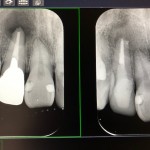

その時の写真をアップします。左の写真が術前です。根の先の黒いのが歯根嚢胞です。右の写真が数ヶ月後です。根の先の歯根嚢胞が無くなっています!

前歯が腫れて痛いので行きつけの歯医者に行ったところ、良く磨いてと言われて治療が終わったが、翌日ひどくなったので再来院してレントゲンを撮った処、腫れの原因は前歯に膿が溜まっていて根の治療が必要だが金属の土台が深く入っている為それは取れないのでオペが必要で、うちでは治療出きない為、大きな病院を紹介されたとの事でした。

インフォームドコンセントの結果、困難な土台を除去する選択をとりました。ただこの治療法を選択する事は経験と技術が必要なのです。もしも結果が悪かった時は、歯を抜く事になってしまうからです。

困難な土台を除去すると、大量の膿が出てきました。この瞬間に治療は成功したと確信しました。